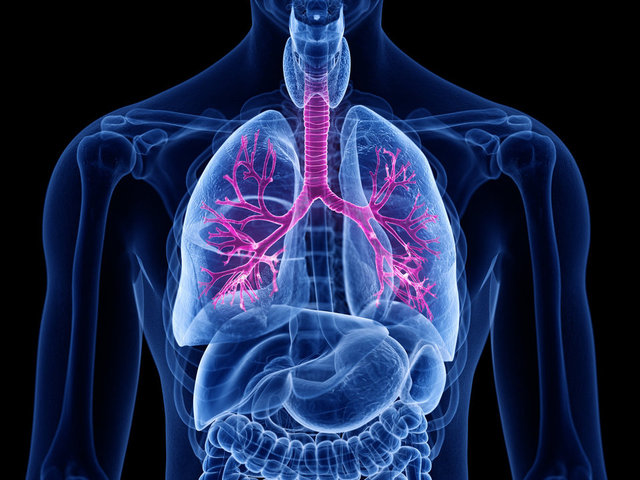

"Akciğer kanseri dünyada giderek artıyor"

Dünyada ve Türkiye´de nedeni belli olan ölümler sıralamasında kardiyovasküler hastalıklardan sonra ikinci sırada akciğer kanseri yer alıyor. Göğüs Hastalıkları Uzmanı Prof. Dr. Ali Metin Görgüner akciğer kanserinin dünyada giderek arttığını ve en yaygın kanser türü olduğunu belirterek 1-30 Kasım Akciğer Kanseri Farkındalık Ayı dolayısıyla açıklamalarda bulundu

Göğüs Hastalıkları Uzmanı Prof. Dr. Ali Metin Görgüner, "Akciğer kanseri tüm kanserlerin yüzde 12-16´sını oluşturmaktadır ve en çok ölüme sebebiyet veren kanser türüdür. Türkiye´de kanser ölümlerinde erkeklerde birinci sırada, kadınlarda ise meme kanserinden sonra ikinci sırada yer alıyor" dedi.